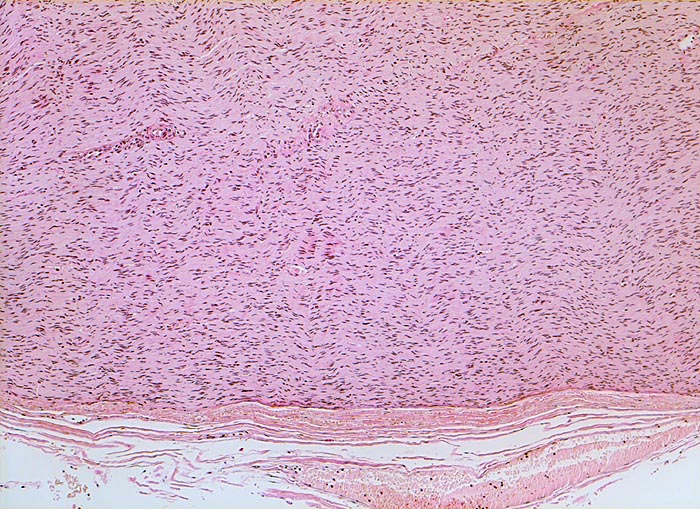

Die histomorphologischen Befunde sind sehr variabel. Am häufigsten bestehen die Tumoren aus Zellzügen mit bipolar orientierten länglichen oder gewellten Kernen und langen Zellfortsätzen. In den sogenannten Antoni A Arealen (> 4295) sind die Zellen in kompakten Bündeln angeordnet, teilweise in Form von Verocay bodies (> 493) (alternierende Anordnung von Kernreihen und Zellfortsätzen). In den Antoni B (> 4296) Arealen bilden die Fortsätze der eher sternförmigen Tumorzellen ein lockeres Geflecht. Einzelne grosse, unregelmässig geformte und hyperchromatische Kerne und flächenhafte Nekrosen, Hyalinisierung oder fokale Verkalkungen sind Ausdruck degenerativer Veränderungen (sogenanntes ancient schwannoma (> 4299)) und dürfen nicht als Zeichen der Malignität fehlinterpretiert werden.

• Biphasischer Tumor mit überwiegend kompakten (Antoni A Muster) und kleinen lockeren, hellen Arealen (Antoni B Muster).

• Antoni B Muster: Lockerer Tumorzellverband mit runden Kernen und spinnwebenartigen Zellfortsätzen.